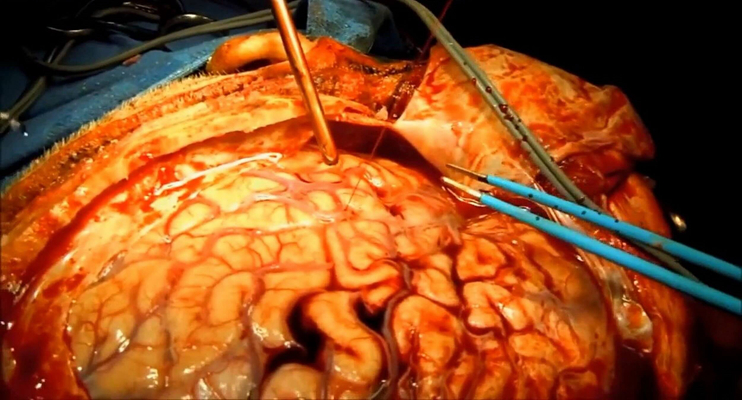

顱內血腫圖片

硬膜下血腫 (7)

硬膜下血腫 (8)

硬膜下血腫 (9)